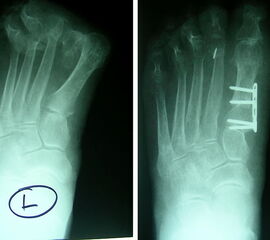

• Röntgenaufnahmen des Fußes in 2 Ebenen stehend (d.p., seitlich).

• Röntgenkontrolle am ersten postoperativen Tag sowie nach 3 und 6 Wochen.

Die basisnahe Crescentic Osteotomie gehört zu den Standardeingriffen zur Korrektur fortgeschrittener Hallux valgus Fehlstellungen. Ein distaler Weichteileingriff sollte routinemäßig mit durchgeführt werden. Die Mobilität des ersten Strahls wird auf ein normales Maß reduziert und ermöglicht wieder eine normale Lastaufnahme 1. Der Intermetatarsale Winkel wird gut korrigiert. Die Verwendung einer winkelstabilen Plattenosteosynthese zur Fixation einer proximalen Osteotomie am MT I hat sich bereits bewährt894. Häufig wird additiv eine Akin Osteotomie durchgeführt. Irritationen über der tastbaren Platte führen in vielen Fällen zur Metallentfernung.